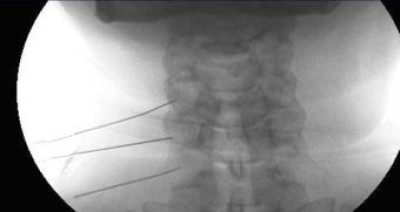

Colocación de Agujas